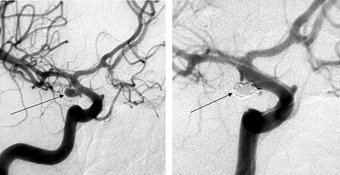

Left: Angiographic view of an aneurysm

Right: Three-dimensional illustration of the same aneurysm

Aneurysm: the neuroradiological treatment by coil embolisation

Coil embolisation is also performed under general anesthesia. A catheter is inserted through the femoral artery and advanced under fluoroscopy to the aneurysm-bearing artery. Subsequently, the aneurysm will be filled with platinum spirals, the so called coils, and therefore taken out of blood circulation.

Advantage of embolization: No opening of the skull required

Disadvantage of embolization: A coil compaction can occur later, therefor always a control angiography must be carried out, sometimes a re-treatment becomes necessary.